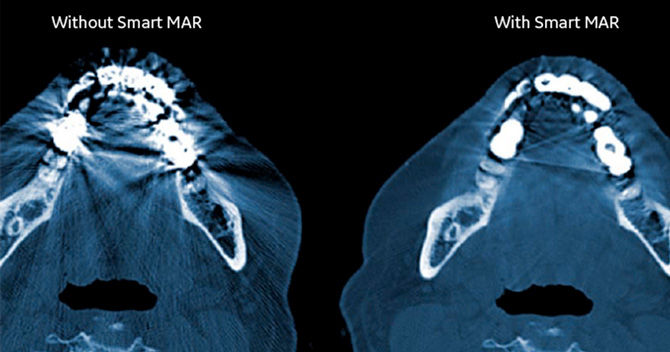

More informed diagnosis with higher imaging intelligence using Smart MAR

Smart MAR is designed to reveal anatomic details obscured by metal artifacts, helping clinicians utilize CT scans, diagnose disease, and contour targets and critical organs with greater confidence.

Using a three-stage projection-based method, Smart MAR helps to reduce photon starvation, beam hardening, and streak artifacts caused by metal in the body. Versatile with exceptional clarity, it requires a single scan for greater speed and efficiency, less patient time, reduced dosing, and increased comfort.